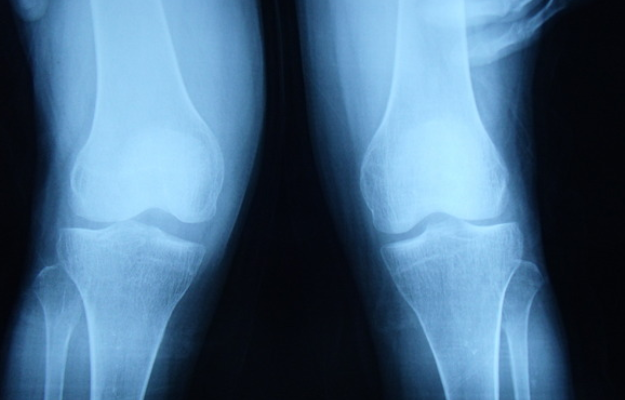

1、前交叉韧带损伤后,膝盖会出现错动感、疼痛感、弹响感,关节活动会受到明显影响,患者不能再继续进行体育活动。

4、如果前交叉韧带损伤后肿胀明显,应该及时就医,通过影像学检查,来确定韧带损伤的程度,同时采取服用消炎止痛类药物(如布洛芬等)、理疗等方法,来防止滑膜炎的发生。